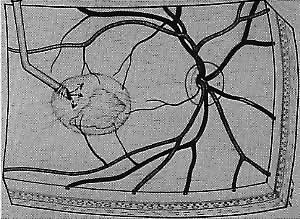

In most cases that meet the criteria for subretinal surgery, the edge of the neovascular complex can be readily visualized under the operating microscope without angiography. In some relatively recent membranes, even if they are anterior to the RPE, we have found the edges to be more difficult to discern. Thus, on occasion, it is helpful to select a frame from the preoperative fluorescein angiogram to project on a screen in the operating room. The image is inverted and reversed to match the surgeon's view through the operating microscope at the top of the patient's head.

A standard three-port approach is used to carry out a complete pars plana vitrectomy. The placement of the sclerotomy is critical. The surgeon should study the angiogram and decide preoperatively where the retinotomy is to be placed to avoid damaging major vessels, to provide adequate access to the subretinal membrane, and to minimize the size of the scotoma. These factors usually dictate that the retinotomy be created in a straight temporal location and thus the superotemporal sclerotomy should be made near the horizontal meridian. If a sewn-on ring system is used to hold a corneal contact lens, it is sometimes advantageous to rotate the fixation flanges superotemporally and inferonasally from the horizontal to allow a nearly horizontal placement of the temporal port. Occasionally these horizontal sclerotomy sites bleed more than when placed more superiorly, but this has not proven to be a significant complication.

The placement of the retinotomy takes into account (1) the exact location of the membrane under the fovea; (2) the presence of presumed adhesions between the neurosensory retina and underlying tissue (previous photocoagulation scars and/or evidence of pigment migration into neurosensory retina or retinochoroidal vascular anastomoses); (3) the dimensions of the subretinal instruments (specifically the length of the angled instrument tips that determines how far away from the fovea the retinotomy can be made and still allow the tips to reach the membrane); and (4) the topographic anatomy of the neurosensory retina and nerve fiber layer. (A retinotomy made temporally in the macula disrupts less nerve fibers than does a retinotomy made nasally or superiorly that risks the creation of an arcuate visual field defect or reduced central acuity secondary to the interruption of the papillomacular bundle.) In most cases, these factors dictate a straight temporal or slightly superotemporal location for the retinotomy. However, the surgeon may choose to create a retinotomy superonasal to the fovea. With newer 33- and 36-gauge instruments, the retinotomies are small enough that no significant damage to the papillomacular bundle occurs. This approach may allow the surgeon to use his or her dominant hand for subretinal manipulation.